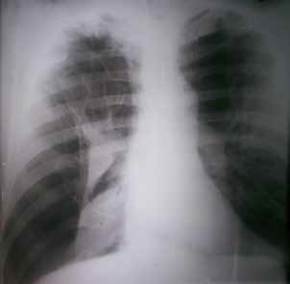

Se retiró la sonda torácica obstruida y se practicó una nueva pleurotomía mínima baja, manteniéndose con una aspiración negativa a -20 cm de agua. El derrame disminuyó considerablemente, pero, al suspender la aspiración negativa, el pulmón colapsó nuevamente. El paciente se negaba a otros procedimientos quirúrgicos, por lo que, mediante consulta con el grupo de especialistas, se decidió optar por una pleurodesis con talco por la sonda, después de la cual, se logró mantener expandido el pulmón (figura 3).

Figura 3. Radiografía de tórax, postero-anterior y en bipedestación, en la que se aprecia la reexpansión del pulmón derecho, además de múltiples bullas enfisematosas en ambos campos pulmonares.